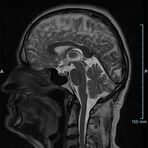

Kopf/Hals

Kopf

• akute Schlaganfalldiagnostik und chronische Durchblutungsstörungen

• entzündliche Prozesse des Gehirns oder der Gesichtsweichteile

• Tumore, ggf. mit Spektroskopie

• Abklärung Schwindel, zentrale Sehstörung, Kopfschmerz

• Metastasenverdacht

• Multiple Sklerose

• Abklärung Hirnnerven, Schädelbasis inkl. Hypophyse

• Abklärung Kleinhirn, Hirnstamm, Halsmark

• intrakranielle Gefäße (Abklärung Verschluss, Stenose, Aneurysma)